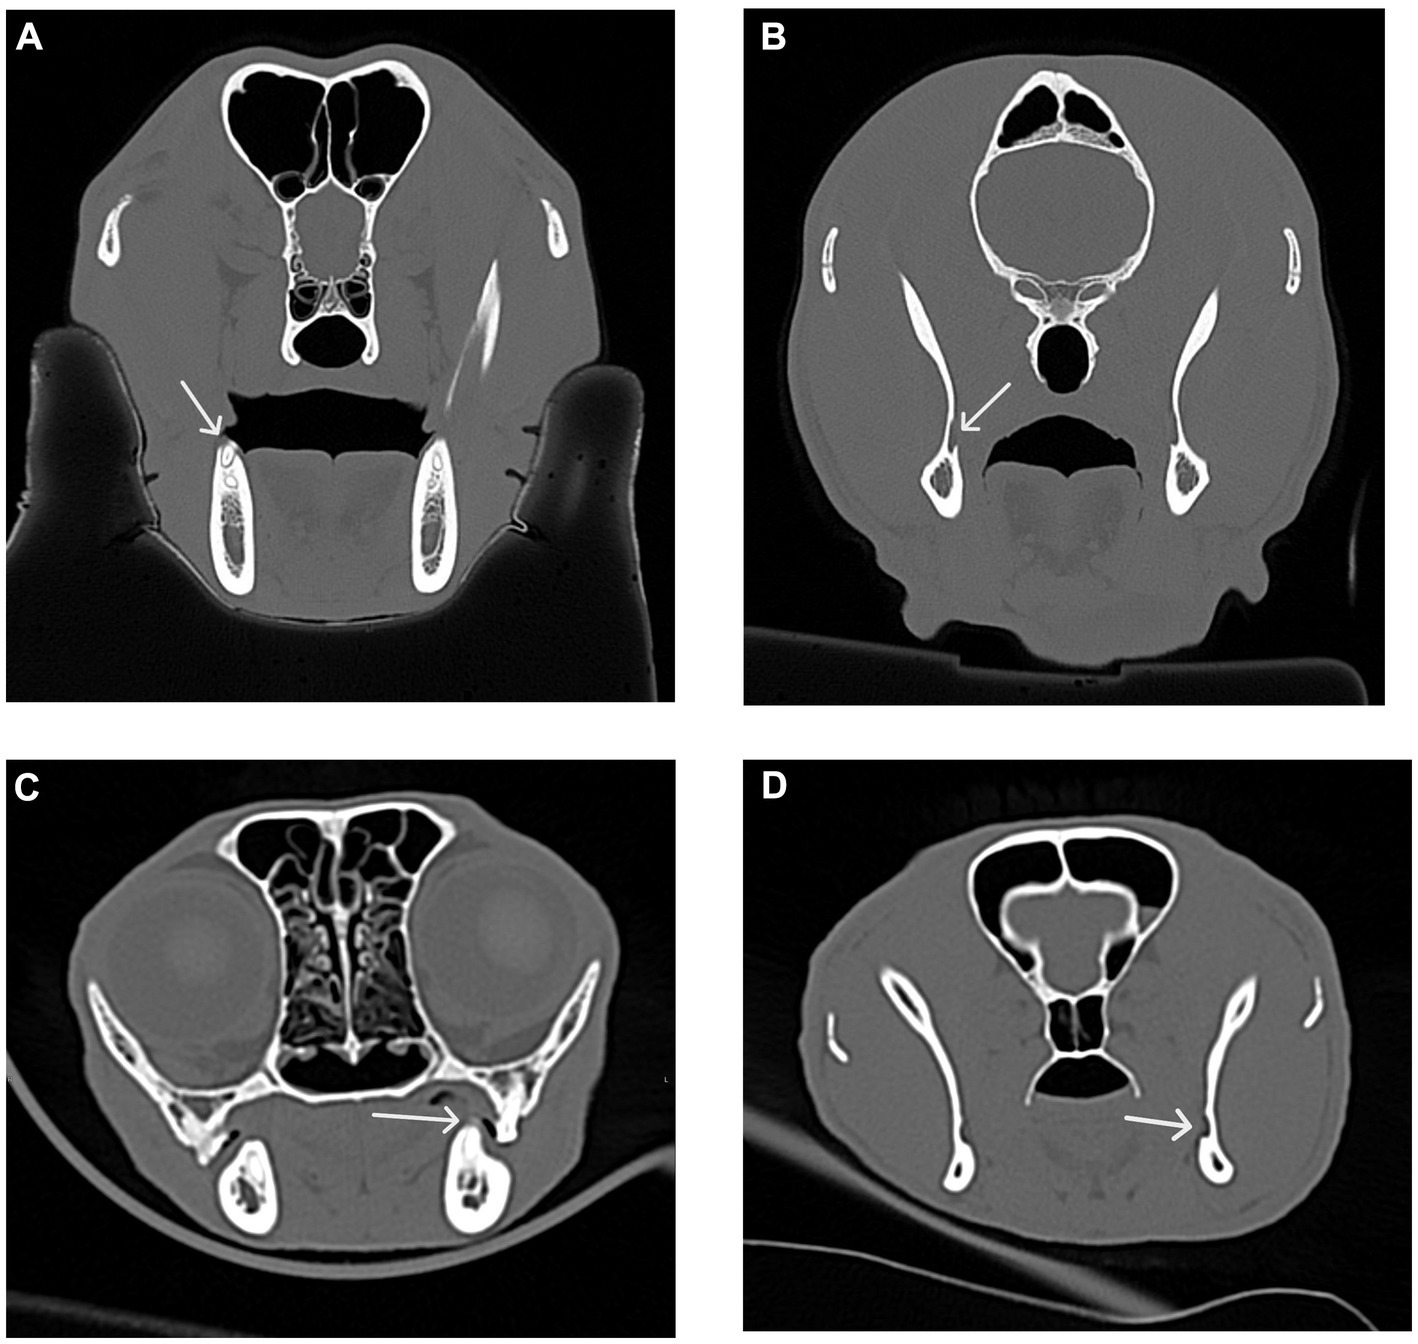

Figure 11

Four-panel CT scans of a dog and cat skulls, labeled A through D. Panel A shows a transverse CT scan of a dog skull with a white arrow indicating the caudal surface of the last right mandibular molar visible as a white tooth-like structure in the right mandible. Panel B shows a transverse CT scan of a dog skull with a white arrow pointing at the right mandibular foramen, visible as an empty black space in the right caudal mandible. Panel C shows a transverse CT scan of a cat skull with a white arrow pointing to the caudal surface of the left mandibular molar, visible as a white tooth-like structure on the left mandible. Panel D shows a transverse CT scan of a cat skull with a white arrow pointing at the left mandibular foramen, visible as a small black empty space on the caudal left mandible.

Figure 11. Transverse CT images were used to measure the distance between the distal crown of the mandibular third molar tooth in dogs and the mandibular first molar tooth in cats to the mandibular foramen. (A) Transverse CT image showing the distal crown of the right mandibular third molar tooth (white arrow) in a dog. (B) Transverse CT image showing the right mandibular foramen (white arrow) in a dog as determined by the first transverse slice with an open mandibular foramen. (C) Transverse CT image showing the distal crown of the left mandibular first molar tooth (white arrow) in a cat. (D) Transverse CT image showing the left mandibular foramen (white arrow) in a cat as determined by the first transverse slice with an open mandibular foramen.

To simulate accidental globe puncture during the intraoral caudal maxillary nerve block, measurements were taken from the caudal border of the palate, immediately caudal to the maxillary second molar tooth in dogs and maxillary first molar tooth in cats, to the closest surface of the globe (palate-to-globe) using sagittal and transverse views (Figures 10C,D). In dogs and cats with a last mandibular molar tooth, the distance from the distal crown surface of the last mandibular molar tooth to the first CT slice with an open mandibular foramen was recorded using the transverse view (Figures 11AD). Accurate distance measurements from the last mandibular molar tooth to the mandibular foramen were not possible on the sagittal view due to the angulation of the mandible. Root length determination for the distal buccal root of the maxillary first molar tooth in the dogs was measured from the cementoenamel junction to the root apex (Figure 12A). Root length determination for the distal buccal root of the maxillary second molar tooth was measured from the horizontal pulp horn to the root apex (Figure 12B). The cementoenamel junction was not as discernible on the maxillary second molar tooth of the dog, so the horizontal pulp horn was used instead. If the distal buccal root length of the maxillary second molar tooth was not visible on a single transverse slice, then the palatal root was measured instead using the technique described in the previous sentence (Figure 12C). All measurements were collected and recorded separately for the left and right sides. Results were grouped and placed in tables according to their use in clinical practice. Minimum and mean distance values of the infraorbital foramen-to-globe, left and right maxillary first and second molar tooth root apex-to-globe, and palate-to-globe distance values in dogs were grouped (Table 1). Minimum and mean infraorbital foramen-to-globe, left and right maxillary fourth premolar tooth root apex-to-globe, and palate-to-globe distance values in cats were grouped (Table 2). Values ≤2.8 mm were highlighted in gray. Minimum, mean, and standard deviation for infraorbital canal length, infraorbital foramen width and height, and percent of animals with a bifurcation of the infraorbital canal for all cats and dogs were grouped (Table 3). Mean distances from the distal crown surface of the last mandibular molar tooth to the mandibular foramen, and palate-to-maxillary foramen for all dogs and cats were grouped (Table 4). The percentage of distal buccal roots fused with the palatal root, and root length measurements for the maxillary first and second molar teeth in dogs were grouped (Table 5). The percentage of teeth in which the globe was centered over was determined for each body weight and skull type (Table 6), with the first and second highest percentage points highlighted in gray. Results of the most likely position of the eye were recorded for 28 dolichocephalic dogs ≤10 kg, 43 dolichocephalic dogs ≥11 kg, 56 mesocephalic dogs ≤5 kg, 56 mesocephalic dogs of 6–10 kg, 64 mesocephalic dogs ≥11 kg, 62 brachycephalic dogs ≤10 kg, and 62 brachycephalic dogs ≥11 kg (Table 6). Results were recorded for 62 MCat and 16 BCat cat eyes (Table 6). Mean, median, mode, minimum, maximum, and standard deviation of the globe diameter for all cats and dogs were grouped (Table 7). Results were calculated for 28 dolichocephalic dogs ≤10 kg, 43 dolichocephalic dogs ≥11 kg, 63 mesocephalic dogs ≤5 kg, 60 mesocephalic dogs of 6–10 kg, 64 mesocephalic dogs ≥11 kg, 62 brachycephalic dogs ≤10 kg dog eyes, 62 brachycephalic dogs ≥11 kg dog eyes, and 62 MCat and 16 BCat cat eyes. Minimum and mean infraorbital canal length, infraorbital foramen-to-globe, and recommended safe catheter or needle insertion length, for the infraorbital and modified infraorbital approach to the maxillary nerve blocks, were calculated for all cats and dogs (Table 8). All dogs below the mean infraorbital length standard deviation value for infraorbital canal length were considered “extreme brachycephalic” by the authors and included French bulldogs and pugs (four animals in total). The authors observed that French bulldogs, pugs, and Boston terriers had similarly shorter infraorbital canal mean lengths of 2–9 mm, across both ≤10 kg and ≥11 kg brachycephalic weight categories. Boston terriers, French bulldogs, and pugs were pooled together in a group labeled “extreme brachycephalic” for a total of 20 animals (14 French bulldogs, 2 pugs, and 4 Boston terriers), and their values are reported in the second-to-last row of Table 8. Minimum and mean infraorbital canal length and infraorbital foramen-to-globe length distances were recalculated for the brachycephalic dogs ≥11 kg dog group, with extreme brachycephalic dogs removed, to reflect a more accurate representation of the infraorbital canal lengths in these groups (Table 8). Groups where both the minimum infraorbital canal length and infraorbital foramen-to-globe distances were less than 10 mm were highlighted in gray to indicate that extreme caution should be used.